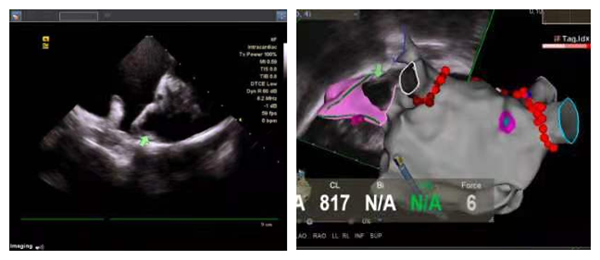

患者连某某,女,83岁,多年来饱受心房颤动的困扰,每于房颤发作时自觉胸闷、心慌显著,并且由于房颤血栓形成导致脑梗死。王洪涛教授接诊患者后,为其进行规范细致的诊疗,经判断,该患者CHADS2评分高达五分,适合进行房颤一站式手术。在进行充分的术前准备后,王洪涛教授行心腔内超声(ICE)指导下射频消融术+左心耳封堵术,历时2小时30分钟。8F超声导管经由房间隔穿刺鞘进入左房进行心耳大小测量、左心耳封堵器位置评估及释放后评估。

心腔内三维超声技术(ICE)是国际心内介入领域兴起的一项新技术。近年来,该技术越来越多应用在“一站式”手术中,使病人免除食道超声痛苦,避免全麻。心腔内超声导管通过患者的下腔静脉血管送入患者心腔内,如同术者的第三只眼睛,帮助看见心脏内解剖结构,实现更精准安全的房间隔穿刺,并且从各个角度灵活自由地评估心耳形态,帮助选择合适大小的封堵器,评估并释放。

此外,三维心腔内超声导管可以帮助医生在极低射线辅助甚至零射线的情况下进行房间隔穿刺。同时术前、术中、术后可做到实时监测心包积液,在患者体征还未出现变化的情况下,依靠相较于射线更高的灵敏度,第一时间发现并处理心包积液,为病患的安全保驾护航。

目前国内的三维心腔内超声有两种型号的导管,常规用的是直径为10F(直径约等于3.33mm)。本次手术中使用的8F三维心腔内超声导管,与10F心腔内超声相比,在保证图像质量,定位精度以及操作体验的前提下,基于8F的心腔内超声导管比传统导管更细、软的特点,它能够:1.为手术操作提供更高的安全保障:对病人的创伤更小,手术出血更少,并发症概率更低,安全性更高。因此不管是对电生理手术还是结构性心脏病手术,都能提供更高的安全性。2.进入左房更容易:在LAAC左心耳封堵中,操作灵活,降低医源性房间隔缺损的风险,保障手术安全性和有效性。3.更适合小儿患者:导管更容易进入体积更小的小儿心腔,手术创伤更小。